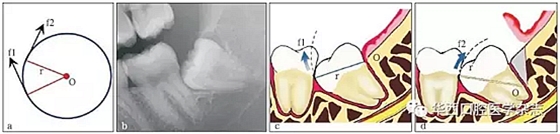

3.3.1 轉(zhuǎn)動軸心與圓弧運動 這一原理在前傾或水平阻生智齒的拔除中運用最廣??梢酝ㄟ^改變牙體轉(zhuǎn)動脫位時的運動軸心,來改變牙體上各點的運動方向(圖 4),從而避開阻力而使牙齒脫位。但在此過程中,牙槽窩的擠壓變形仍不可避免。尤其是舌側(cè)骨板的骨折,更是經(jīng)常發(fā)生的事件。要進一步減少對牙槽窩的擠壓,則需要對牙根進行進一步的切割。

在圓周運動(旋轉(zhuǎn))中,圓周上所有點的運動方向(f1、f2)均為切線方向,與通過該點的半徑(r)相垂直(圖a)。當(dāng)牙齒發(fā)生旋轉(zhuǎn)脫位時,其阻力點的運動方向會隨著轉(zhuǎn)動的軸心點的變化而變化,從而避開阻力。前傾阻生智齒(圖b)脫位時,阻力分析如圖 c所示,因阻力點位于旋轉(zhuǎn)中心(O)的下方,旋轉(zhuǎn)脫位時,其阻力點的運動方向(f1)是向前上的,被鄰牙所阻擋。如果按照圖 d所示,去除遠中骨質(zhì)(灰色部分)或切割牙體(r)后,旋轉(zhuǎn)中心(O)下移,阻力點的運動方向就改變?yōu)橄蚝笊希╢2),而得以避開鄰牙阻擋而脫位。

圖4 轉(zhuǎn)動軸心與圓弧運動